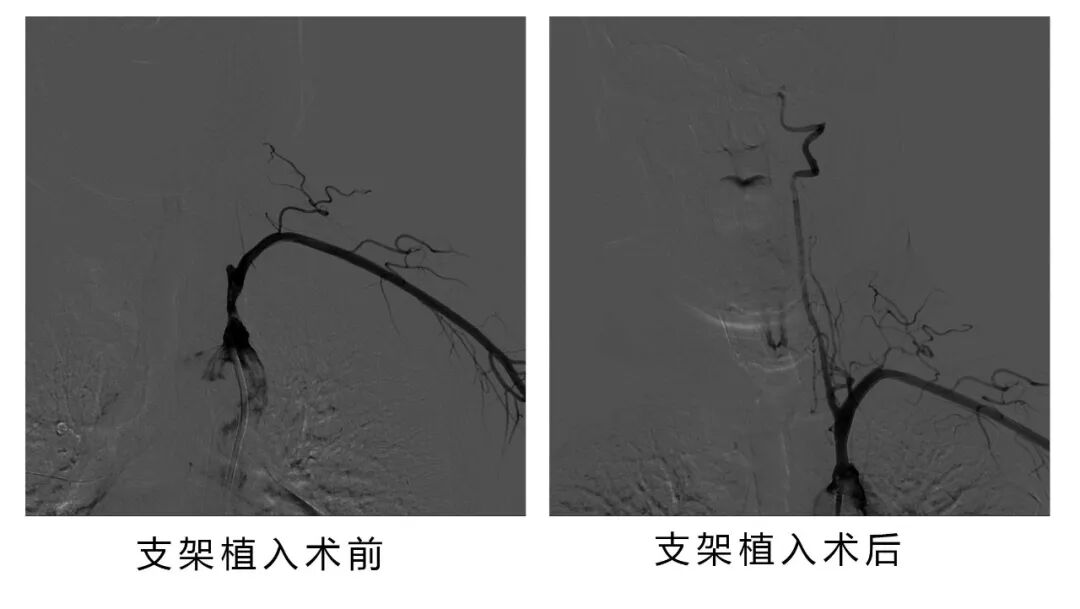

手术了270分钟,射线为2070,顺利完成锁骨下动脉闭塞开通手术。

此时贾颐主任带领团队并无退缩并无放弃,经过大量的准备工作后,为患者行经皮右侧股动脉穿刺+经左侧桡动脉穿刺选择性脑血管造影+左侧锁骨下动脉闭塞再通术(球囊扩张+支架植入)。经过介入团队近5个小时的努力,期间也曾多次行导丝通过困难,多次球囊扩张不满意,但是在贾颐主任的不懈努力下,最终血管成功开通!